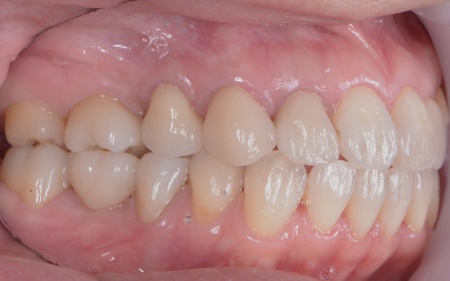

| カウンセリング | 拝見したところ、左下と右上の歯はともに大きな虫歯があり、歯だけでなく被せ物を支える土台の部分にも影響が及んでいました。

さらに、ほかの歯に入っている詰め物や被せ物の周囲にも、過去に治療した部分に再び虫歯ができる二次カリエスが複数見つかりました。 また、噛み合わせを確認したところ、奥歯で噛み合わせた際に上下の前歯が当たらず隙間ができる開咬(かいこう)が認められました。 実際に患者様の場合も、特定の歯に長期間強い力がかかり続けたことで歯や修復物の破損、さらには口腔内全体のトラブルにつながった可能性が高いと考えられました。 修復治療が必要でしたがこの噛み合わせの問題を改善しないまま行うと、治療した歯に再び過度な力が加わって被せ物の破損・脱離や虫歯の再発を招くリスクが高まります。 |

まずは矯正治療を優先し、噛み合わせが整ってから虫歯の再発リスクの低いセラミックの被せ物・詰め物などで歯の形態と機能を回復する方針を提案し、同意いただきました。

矯正治療については、専門的な診断と管理が必要と判断したため専門の矯正歯科医院をご紹介し、他院にて実施していただきました。 矯正治療終了後、改めてお口の中を確認したうえで、歯の状態に合わせ虫歯の除去や土台の修復を丁寧に行い、精密な型取りを実施しています。 最後に噛み合わせ全体のバランスを確認しながら新しく作製した被せ物や詰め物を装着し、見た目に問題がないか、噛み合わせが安定しているかを確認し、治療を終了しました。 |